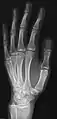

• Hand - DP and Oblique

• Fingers - DP and Lateral

• Thumb - AP and Lateral